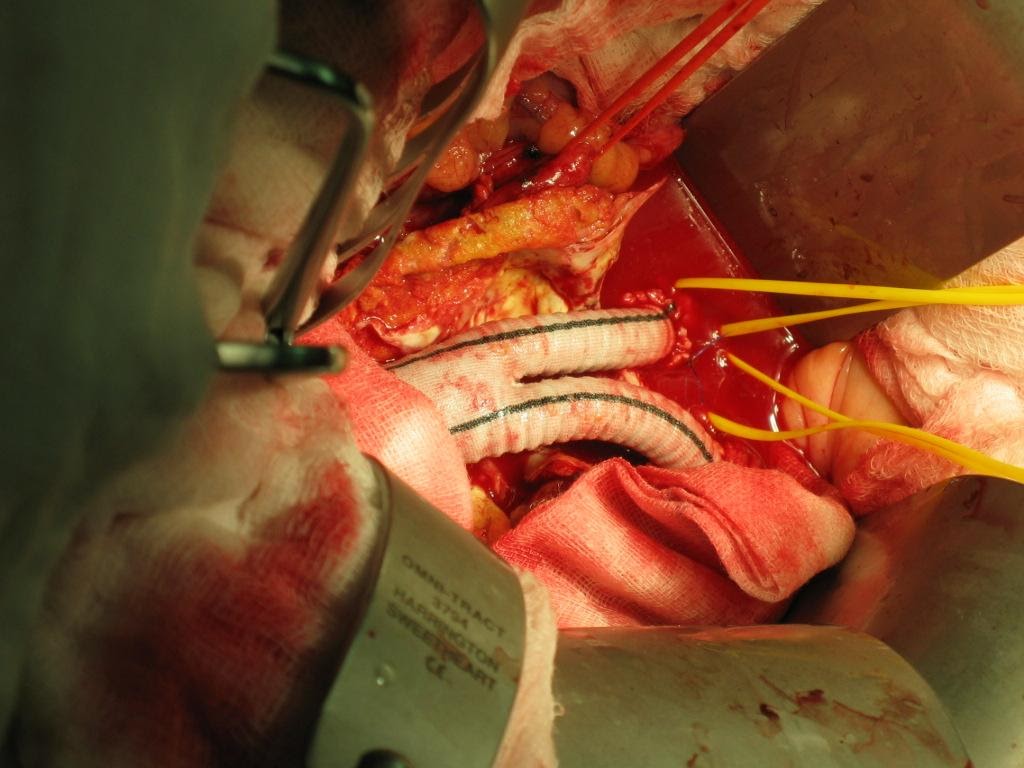

Ever since Juan Parodi put in the first stent graft in an Abdominal Aortic Aneurysm patient during 1990s, the status of open repair and inlay grafting (Figure 5,6) of Abdominal Aortic Aneurysm as gold standard has been challenged.

Figure 6: Intra-op picture of Inlay-graft

Open repair of Abdominal Aortic Aneurysm involves laparotomy, retroperitoneal access, cross clamping of aorta proximal and distal to aneurysm followed by aneurysectomy and inlay grafting. The peri-operative mortality started from 10% and surges with various co-morbid factors. It is not uncommon for a 70 years old AAA patient to present with Hypertension, Diabetes mellitus and Ischemic Heart Disease, as such the peri-operative mortality can be as high as 30-40%. The situation will be worst if patient first presented with leaking or contained ruptured AAA. Prolonged ICU stay post op with ventilator and dialysis support is needed in some cases.

At the other hand EVAR procedure (Figure 7,8) involves access to femoral artery by cut down or percutaneous method, wiring into ascending aorta, tracking delivery device up into the aneurysm, stent graft deployment and then repairing the access femoral artery. The procedure avoided cross clamping of aorta and reduces blood loss intra-operatively. This help to maintain the hemodynamic during aneurysm repair, and hence reducing the stress to cardio-vascular system and to the patient as a whole.